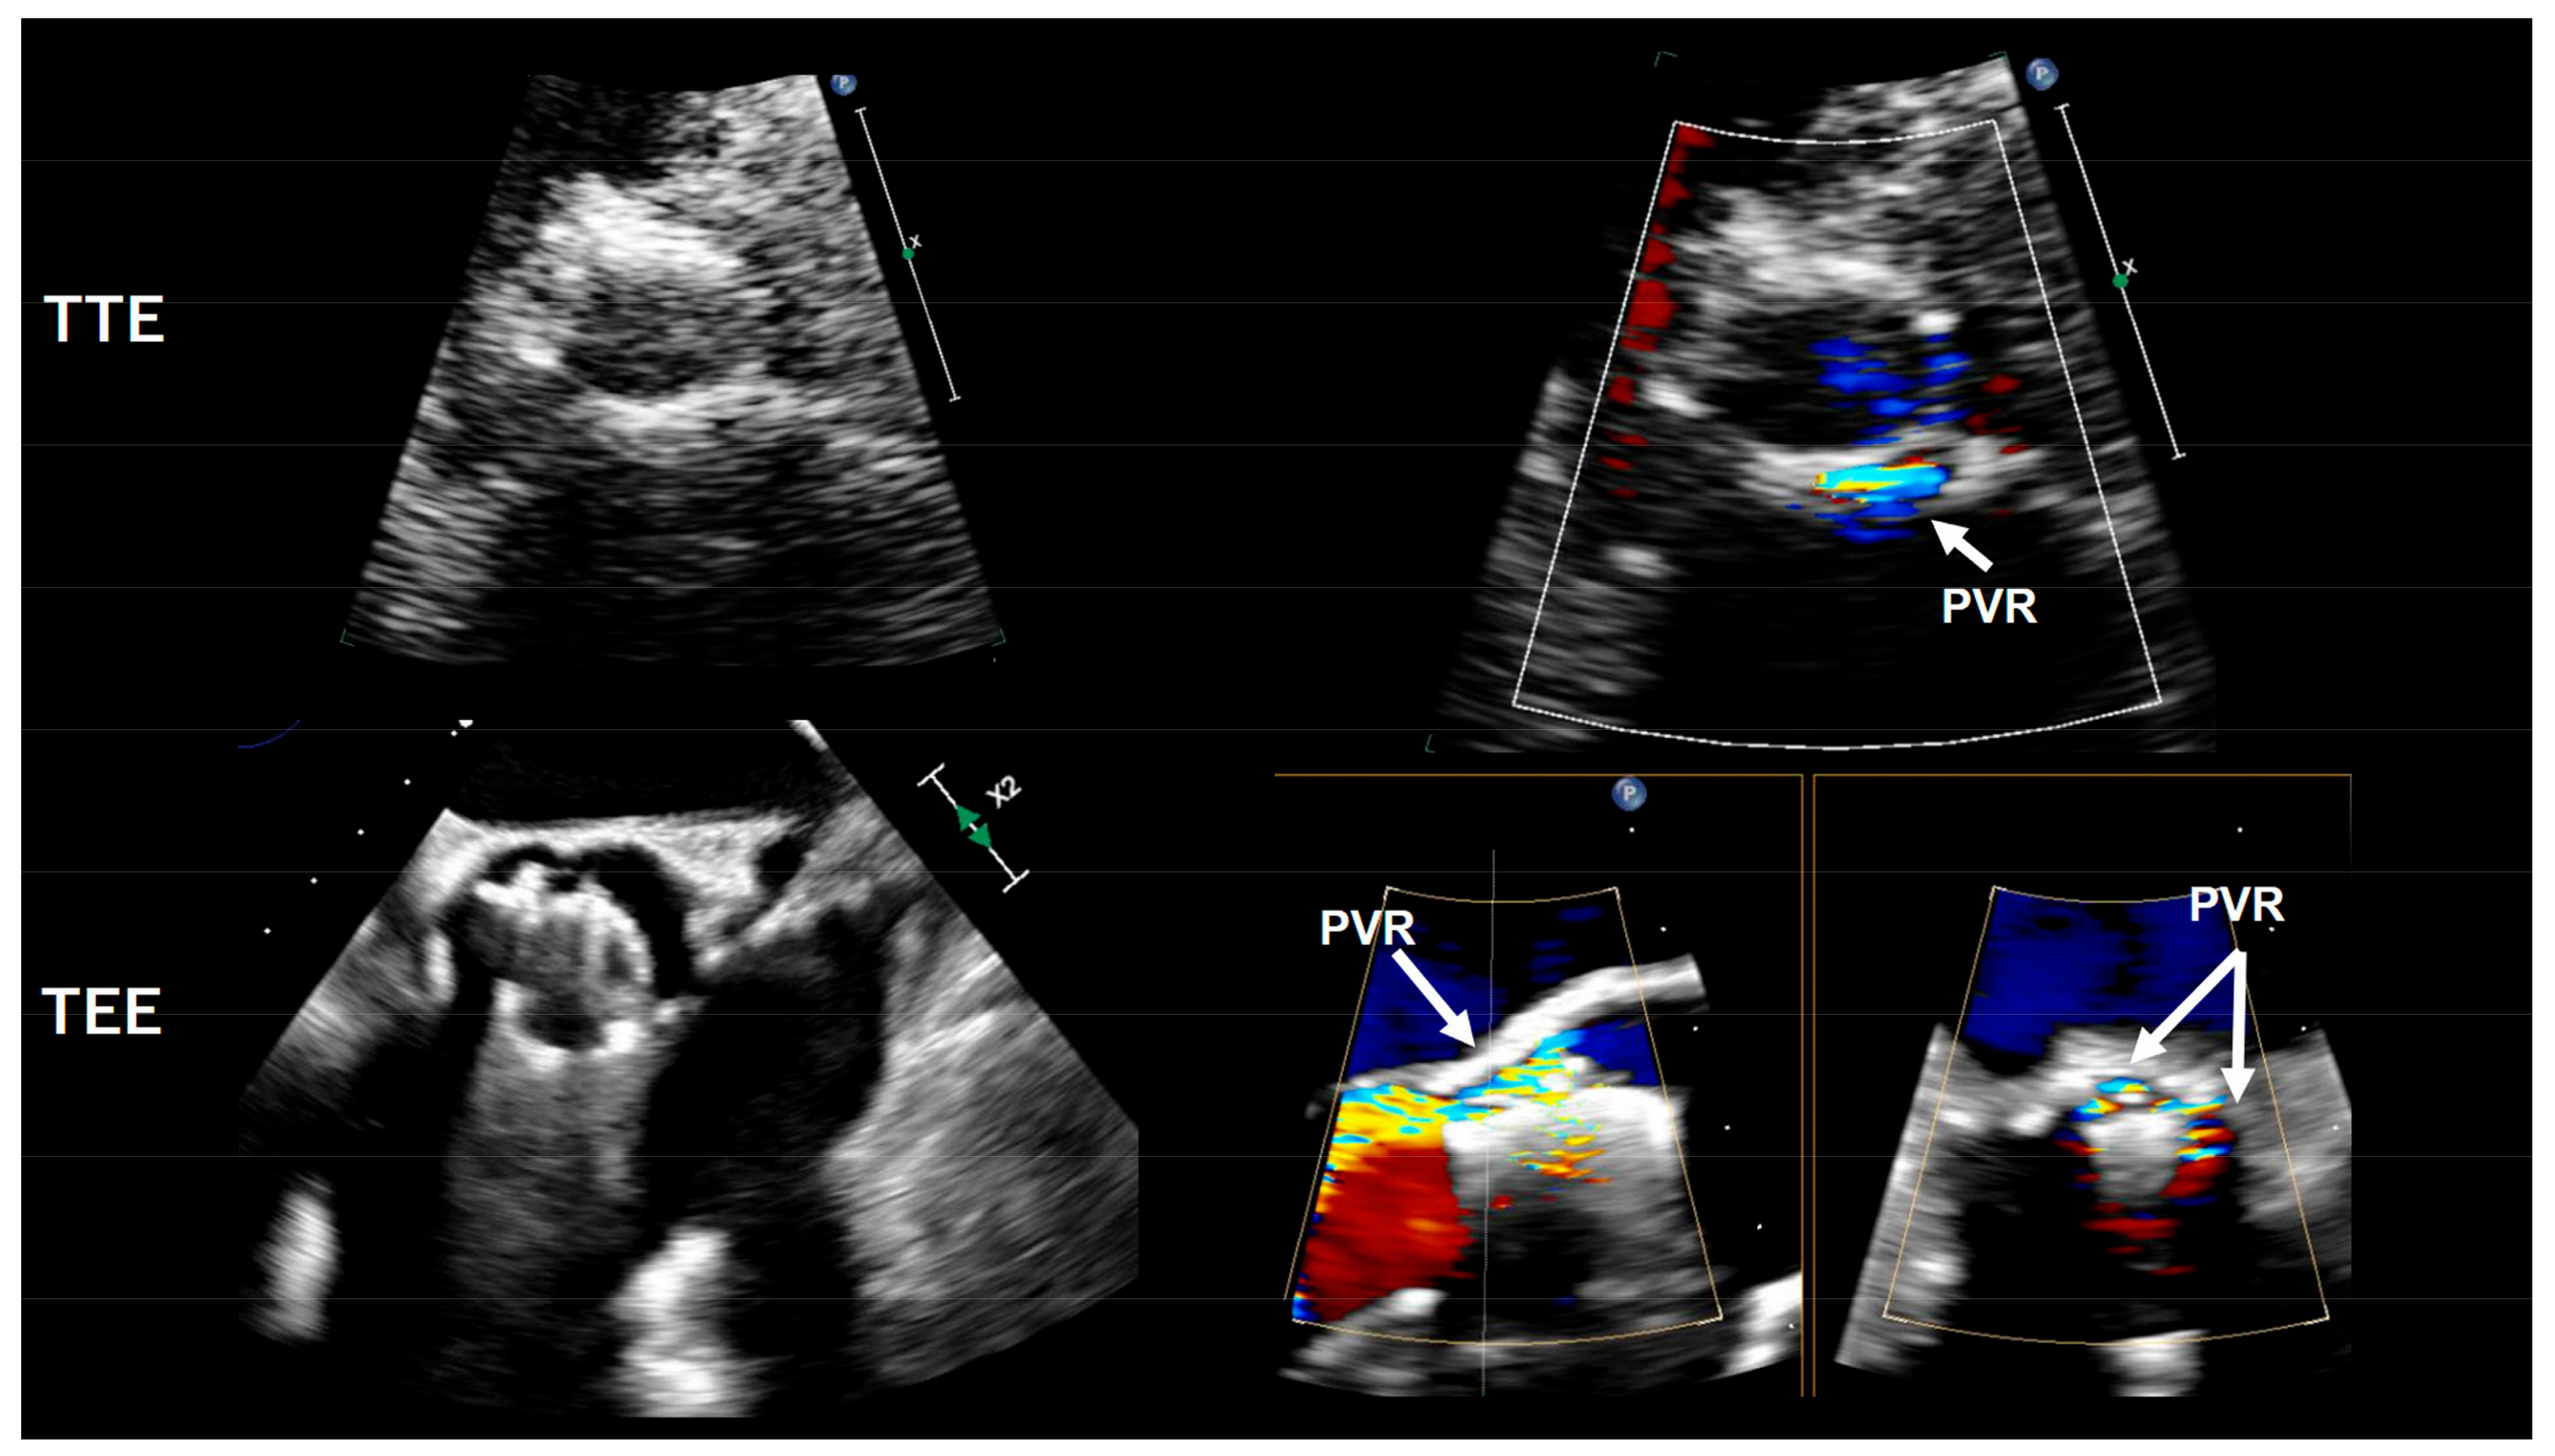

3.1. Paravalvular Regurgitation (PVR)